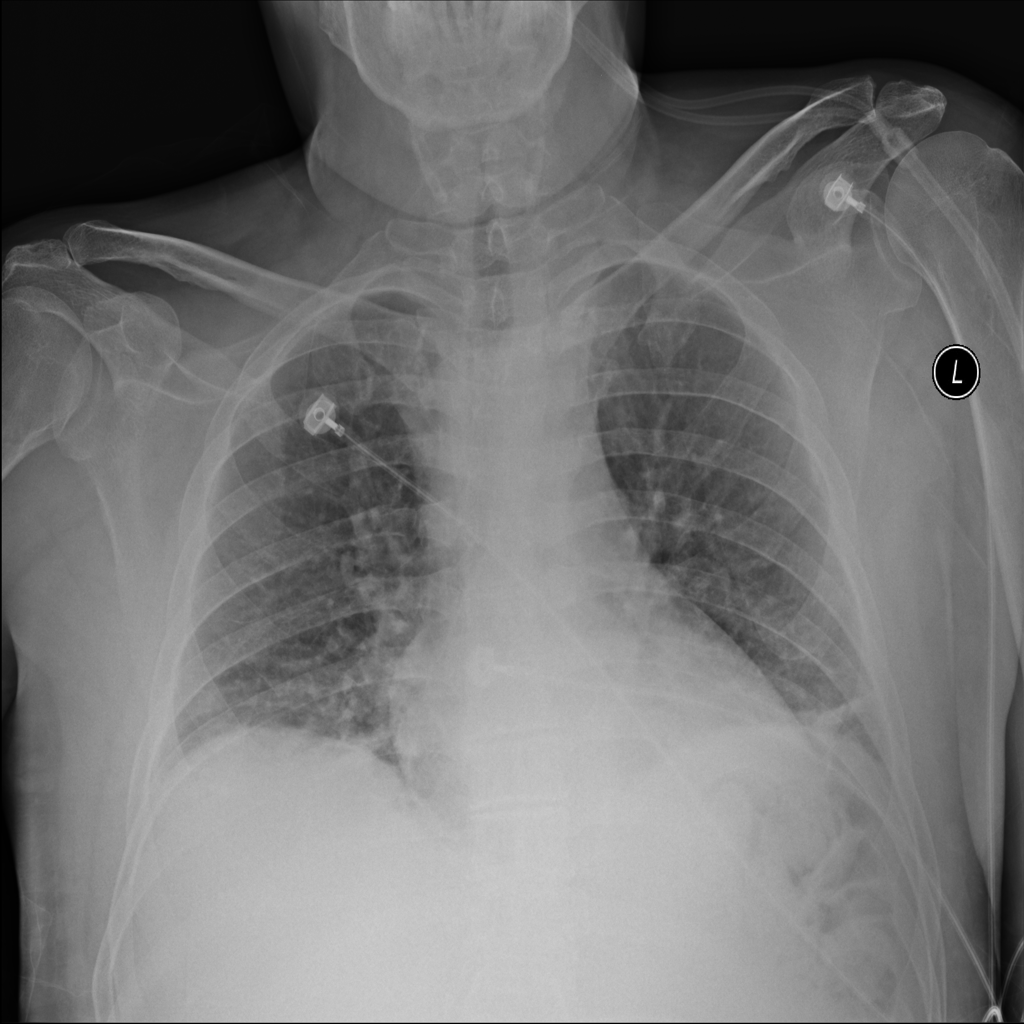

PAT-4639 · IMG-013Pneumothorax

PAT-4639 · IMG-013

AP